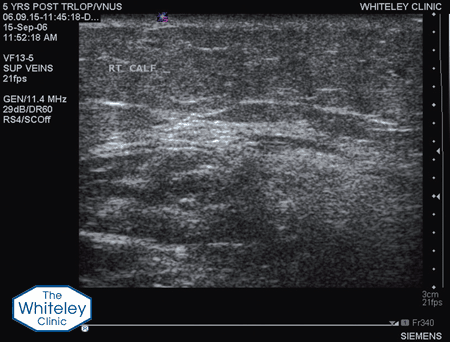

Due to our research and understanding of incompetent perforating veins, and our invention of the TRLOP minimally invasive technique of treating them, all The Whiteley Clinic patients with varicose veins or other venous problems have their incompetent perforating veins treated, if they are significant. This is one of the major reasons for the success of The Whiteley Protocol® and the very low longterm recurrence rates at The Whiteley Clinic and high patient satisfaction.